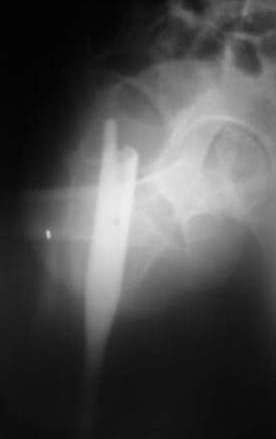

Мы закончили репозицию отломков бедренной кости в аппарате (рис. 1, 2) у нашей пациентки и на прошлой неделе сделали ей вторую операцию. Штифт удалось ввести закрыто. Верхний шеечный винт держался очень плохо, поэтому мы его убрали и решили не ставить. Нижний держал очень плотно. Рентгенограммы после операции прилагаю (рис. 3,4). Пока не получилось сделать нормальный аксиальный снимок (больная с трудом сгибает и отводит ногу в тазобедренном суставе). Пока сделали боковую проекцию в положении на здоровом боку со сгибанием здоровой ноги.